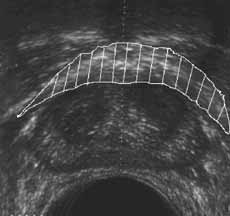

Внутриполостное ультразвуковое исследование в диагностике рака мочевого пузыря и предстательной железы.

Рис. 13 и 14. (Слева) Фиброзно-мышечная строма предстательной железы. (Справа) Капсула предстательной железы.

Новости лучевой диагностики 2001 1-2: 40-46